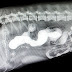

Montecito Pet Hospital Video